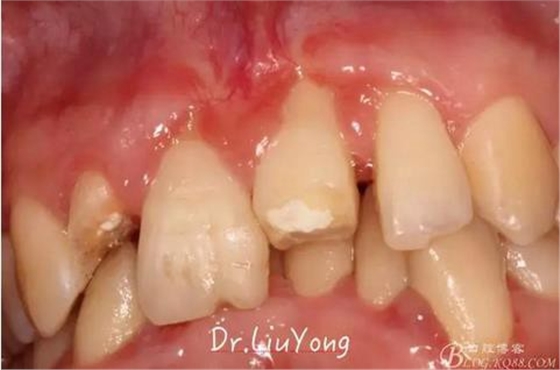

系帶手術后兩周,進行上頜前牙唇側的牙齦退縮的手術治療,由于局部附著齦缺如及牙齦厚度不足,因此同期進行上皮下結締組織移植,解決附著齦及牙齦厚度不足的問題。

術中,可見明顯的唇側骨開裂,如上圖